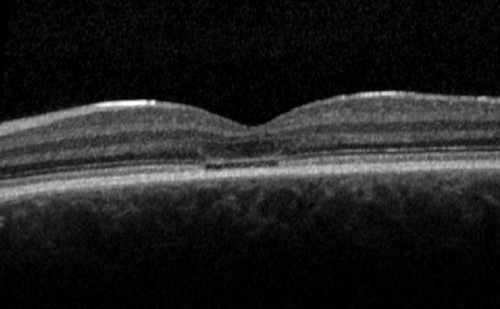

Figure 2: Fundus autofluorescence imaging in a patient with Stargardt disease. Red arrow: increased and decreased autofluorescence in areas where flecks are present; Yellow arrow: reduced autofluorescence at the central macula; Blue arrow: surrounding area of increased signal.

Over 900 disease-causing sequence variants have been identified in ABCA4 to date, resulting in marked phenotypic heterogeneity including variable age of onset and severity [19,20]. Typical presentation occurs during the first or second decade of life with bilateral central visual loss and dyschromatopsia. Earlier onset (childhood-onset STGD) is associated with a worse prognosis and more severe ABCA4 sequence variants, compared to later onset (adulthood-onset STGD and foveal-sparing STGD) [13]. Fundus appearance may be normal in the early stages, with development of increasing macular atrophy / bull’s-eye maculopathy, and yellow-white flecks at the level of the RPE which are associated with characteristic areas of increased and decreased autofluorescence (Figure 2), which changes over time. Spectral-domain optical coherence tomography (SD-OCT) shows loss of outer retinal architecture at the central macula [21].